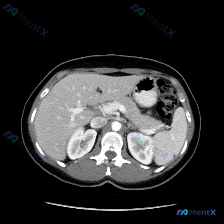

看到一个病例资料挺有意思,整理了一下思路和大家讨论。 用户最初的问题是“图中观察到的特定异常是什么?脾脏病变”,等于先给了一个“存在脾脏病变”的前提。但拿到这张上腹部CT横断面图像(倾向于增强扫描的动脉期或门脉期),仔细看下来,情况其实不太一样。 --- 先看影像层面的客观发现: - 扫描质量与层面...

最近看到一个有意思的影像病例,预设是要讨论「脾脏病变」,但看完影像报告和分析后,发现核心其实是「澄清矛盾」,整理一下思路和大家分享。 --- 先看完整的影像观察结果 这是一份腹部CT横断面的分析: - 实质脏器:肝、胰、脾、肾都大致正常——肝脏密度均匀,胰周脂肪间隙清晰,脾脏形态/大小正常、密度均匀...

今天看到一个有意思的影像读片案例:提问直接预设了“脾脏病变”,但仔细看完提供的资料,发现情况好像不太一样。整理了一下思路,和大家分享。 先看影像资料(客观描述) 这是一张上腹部CT横断面软组织窗影像,报告里的客观表现: - 肝脏:形态尚可,密度基本均匀,未见明确异常高低密度占位,边缘清晰,血管走行正...

今天看到一份很有意思的影像资料,提问直接指向“脾脏特异性异常”,但仔细读完图像和分析,发现里面藏着一个很典型的临床思维陷阱,整理一下思路和大家分享。 先看这张CT的客观发现 这是一张腹部CT横断面软组织窗图像: 1. 脾脏:形态可见,密度均匀,没有看到明确的增大,也没有局灶性的高低密度病变; 2....

整理了一份有点「反转」的影像读片资料,感觉挺考验临床思维的,分享出来一起理理思路。 --- 一、影像基本信息 这是一张腹部CT横断面软组织窗图像,预设的观察焦点是「脾脏病变」。 二、结构化读片所见(客观描述) 按照读片常规扫了一遍全腹: 1. 肝脏、胆囊、胰腺:形态、大小、密度都正常,轮廓光滑,胰周...

今天看到一个很有意思的影像分析场景,整理一下思路和大家分享。 --- 病例背景 用户提供了一张腹部CT横断面(软组织窗),并直接询问:“图片中可见的特殊异常是什么?脾脏病变”。 影像核心表现 我先按标准流程梳理了这张CT的关键信息: 1. 脾脏:大小、形态正常,脾实质密度均匀,明确未见占位、梗死或异...